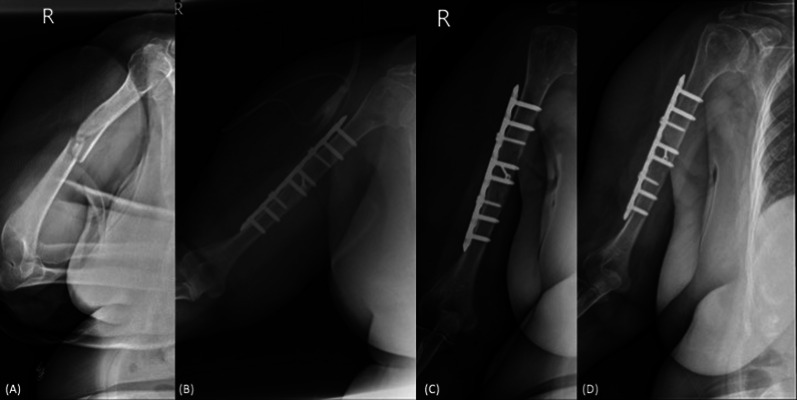

背景:肱骨骨干骨折(HDFs)术后延迟愈合的危险因素尚不清楚。因此,本研究旨在评估一组接受切开复位钢板固定(ORPF)治疗急性HDFs患者的放射学结果和延迟愈合相关的危险因素。材料和方法:2017年至2020年期间,采用标准压缩技术连续接受ORPF的AO/OTA 12-A和AO/OTA 12-B骨折患者纳入研究。收集了人口统计数据以及一系列医疗记录和x射线照片。纳入的患者分为及时愈合组(术后6个月内愈合)和延迟愈合组(术后6 ~ 12个月愈合)。检查各组之间的差异,随后应用逻辑回归进行危险因素分析。结果:纳入病例65例,男34例,女31例,中位年龄38.9岁。其中及时愈合组45例(69.2%),延迟愈合组20例(30.8%)。总体而言,30例(46.2%)表现为继发性骨愈合。在骨折类型、术后即刻骨折间隙、愈合模式和并发症发生率方面,组间观察到显著差异(p)。结论:在急性hsf的ORPF治疗中,尽管使用标准压迫技术,65例患者中有30例出现继发性骨愈合。骨折段间螺钉的应用可显著降低延迟愈合的风险。相反,术后并发症的出现与延迟愈合的可能性增加有关。所有程序均经作者所在医院机构审查委员会批准(IRB号:A-ER-112-395和IRB20230089)。

Background: The risk factors related to delayed union in humeral diaphyseal fractures (HDFs) following surgical osteosynthesis remain unclear. Therefore, this study aimed to evaluate radiological outcomes and the risk factors associated with delayed union in a retrospective cohort of patients who underwent open reduction and plate fixation (ORPF) for acute HDFs.

Materials and methods: Consecutive patients with AO/OTA 12-A and AO/OTA 12-B fractures who underwent ORPF using standard compression techniques between 2017 and 2020 were enrolled in the study. Demographic data, along with serial medical records and radiographs, were collected. The included patients were divided into two groups: the timely union (union occurring within 6 months postoperatively) and the delayed union group (union occurring between 6 and 12 months postoperatively). Differences between the groups were examined, and logistic regression was subsequently applied for risk factor analysis.

Results: Sixty-five cases were included in the study, consisting of 34 males and 31 females, with a median age of 38.9 years. Among these, 45 cases (69.2%) were classified in the timely union group, while 20 cases (30.8%) were classified in the delayed union group. Overall, 30 cases (46.2%) demonstrated secondary bony union. Significant differences were observed between groups in terms of fracture pattern, immediate postoperative fracture gap, union pattern, and complication rate (p < 0.05 for all comparisons). Multivariate logistic regression analysis revealed that the use of interfragmentary screw and the presence of postoperative complications were independent predictors of delayed union, with an adjusted odds ratio of 0.14 and 5.76, respectively.

Conclusions: In ORPF for acute HSFs, 30 out of 65 cases demonstrated secondary bone union despite the use of standard compression techniques. The application of interfragmentary screws significantly reduces the risk of delayed union. Conversely, the presence of postoperative complications is associated with an increased likelihood of delayed union.